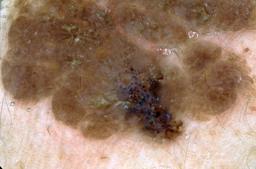

{

"age_approx": 30,

"anatom_site_general": "anterior torso",

"concomitant_biopsy": true,

"dermoscopic_type": "contact non-polarized",

"diagnosis_1": "Benign",

"diagnosis_2": "Benign melanocytic proliferations",

"diagnosis_3": "Nevus",

"diagnosis_4": "Nevus, Atypical, Dysplastic, or Clark",

"diagnosis_5": "Nevus, Dysplastic",

"diagnosis_confirm_type": "histopathology",

"image_type": "dermoscopic",

"lesion_id": "IL_7739720",

"melanocytic": true,

"patient_id": "IP_2399288",

"sex": "female"

}